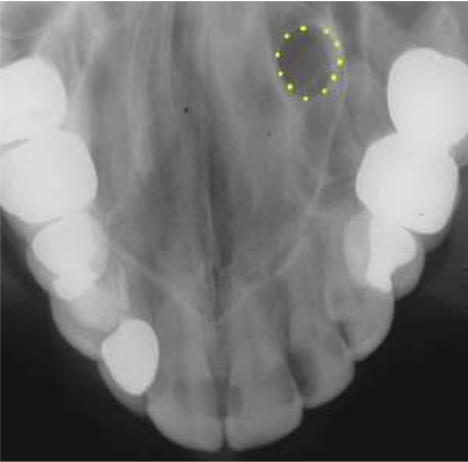

66. 下列何者為附圖中黃圈區域所指的解剖構造?

(A)門齒孔(incisive foramen) (B)鼻腭管(nasopalatine canal) (C)鼻淚管(nasolacrimal canal) (D)上顎竇緣(border of maxillary sinus)